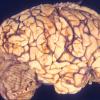

MYELIN (IMMUNE-MEDIATED)

AHL

AHL (3)